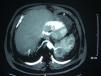

We present the case of a 64-year-old man, ex-smoker, with clinical indicators of chronic bronchitis. He had been on home oxygen for more than 10 years and was on treatment for sleep apnoea-hypopnoea syndrome (SAHS) with nocturnal continuous positive airway pressure (CPAP). He was admitted in 1990 for pneumonia in the left lower lobe (LLL), secondary to symptoms of near-drowning in seawater. During the follow-up, triangular consolidation persisted in the LLL, but both computed tomography (CT) and fibrobronchoscopy failed to provide a diagnosis. CT-guided transthoracic needle aspiration was performed, with cytology negative for malignancy and a negative microbiological study. The patient was admitted on several occasions in recent years for exacerbation of COPD. A new chest CT scan was requested in 2004 due to consolidation in the LLL, and he was diagnosed with possible left intralobar pulmonary sequestration (PS). The patient refused any further studies. In 2009, he was admitted for pneumonia. The chest CT scan (Fig. 1) showed a 6–7-cm complex formation, in a medial location in the LLL, supplied by a large vessel originating in the inferior thoracic artery with drainage to pulmonary veins, corresponding to an intralobar PS with probable superinfection; in a symmetrical location, contralateral, there was another abnormal vessel, also originating in the aorta, corresponding to another intralobar PS in the right region. After improvement with treatment, he was discharged for follow-up at the clinic, but did not attend his check-ups. Most intralobar PS are unilateral, and bilateral PS are very rare.1 For Kohler, PS was first described by Rokitanski and Rektorzik in 1861, but it was not until 1946 when Pryce2 made it known as a clinical entity. In 1972, Felson et al.3 reported a case of bilateral PS confirmed by pathological examination. In 1977, Karp et al.1 described another case in a 13-year-old girl who presented a mass in the LLL, discovered after a chest radiograph. CT scanning and pulmonary arteriography were carried out, showing a left intralobar PS, already suspected, and a right PS that was not previously observed. A few cases have been published since then, similar in that they concern paediatric or adolescent patients. In 2009, Yamamura et al.4 explained the surgical procedure performed on a 44-year-old patient who presented bilateral intra- and extralobar PS. Wei and Li5 analysed 2625 cases of PS in 2011, among which only 3 were bilateral and 2 of these intralobar. The case presented is doubly unique in that this is an older patient with bilateral intralobar PS. He presented recurrent pneumonia with a changing aspect in the LLL, in which diagnostic tests were inconclusive. The possibility of PS had already been described in the CT scan prior to his current admission. The existence of recurrent consolidations, especially if they occur in the LLL, requires us to consider the differential diagnosis of various conditions such as PS, long-standing pneumonia, chronic obstructive disease or lung tumours.6 The diagnosis of PS has traditionally required pulmonary angiography to demonstrate abnormal vascularisation. However, new techniques such as next-generation CT angiography enable high resolution vascular reconstructions that could circumvent arteriography, as well as revealing congenital malformations, thereby avoiding more invasive techniques. With respect to treatment, we would propose acting on the left PS (as it is the symptomatic one) using surgery or VATS, the latter technique being less invasive.